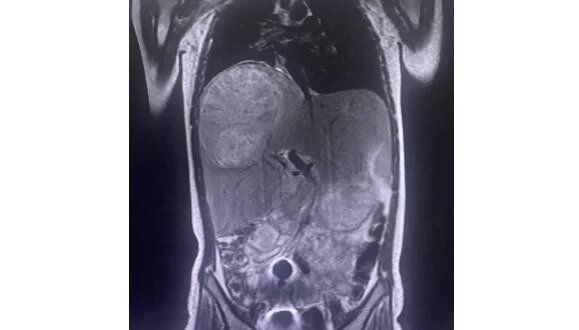

Обследование выявило многокамерный абсцесс правой доли печени размером 10-12 см. Образование поразило три четверти органа и начало сдавливать соседние. Пункция была бесполезна из-за структуры абсцесса. Единственным шансом было полное удаление правой доли печени вместе с нагноением, чтобы не допустить его разрыва.